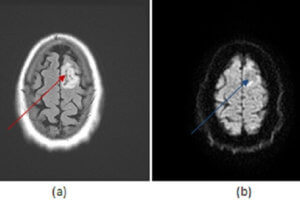

Astrocytoma

Neoplasms of the astrocytes (astrocytomas), are the most common form of primary brain neoplasm. The prognosis for astrocytomas depends on their grade and is better for low grade than high grade neoplasms. Read more »